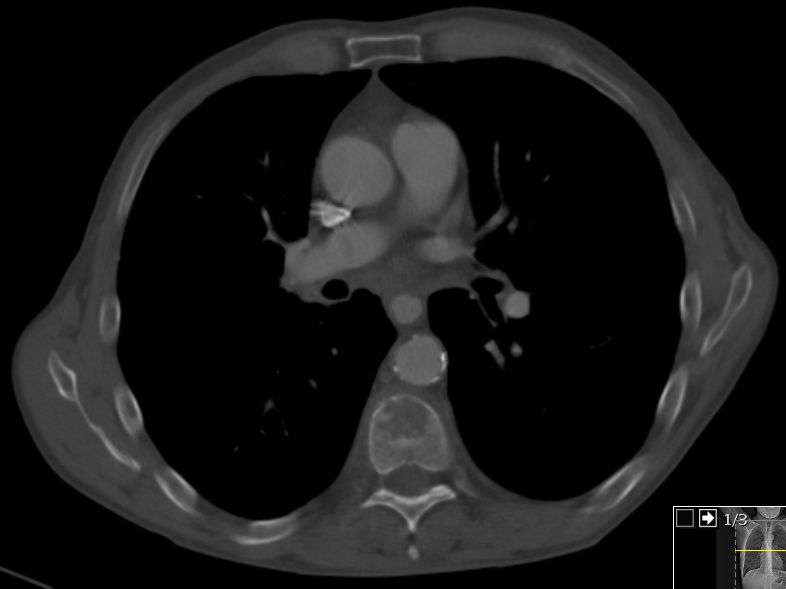

LK-Metastasen im aorto-pulmonalen Fenster ![]() | ||